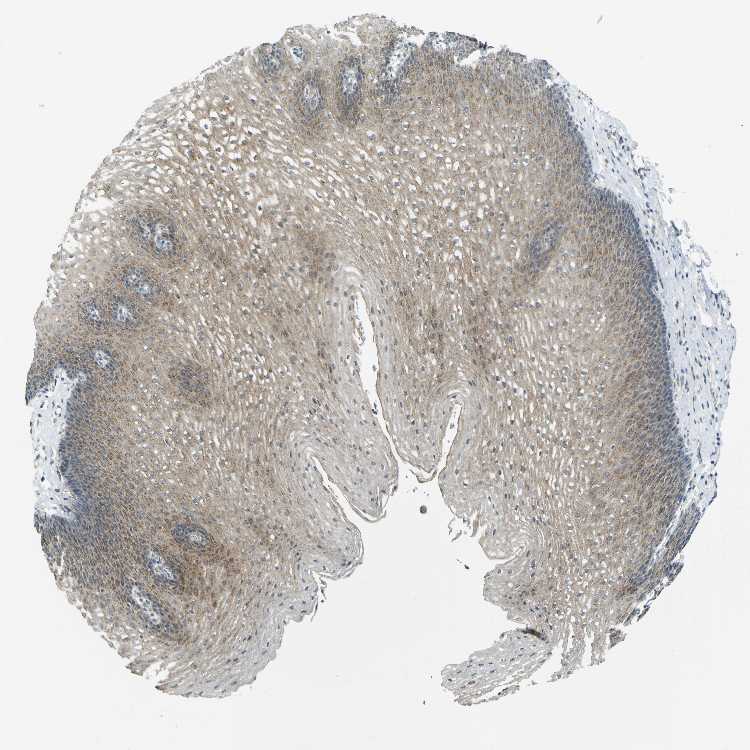

ESOPHAGUS - Antibody stainingi

Antibody staining in the annotated cell types in the current human tissue is reported as not detected, low, medium, or high, based on conventional immunohistochemistry profiling in selected tissues. This score is based on the combination of the staining intensity and fraction of stained cells.

Each image is clickable and will lead to virtual microscopy that enables deeper exploration of all samples and also displays staining intensity scores, fraction scores and subcellular localization as well as patient and tissue information for each sample.

Antibody HPA011861Antibody HPA012145

Squamous epithelial cells MediumMedium